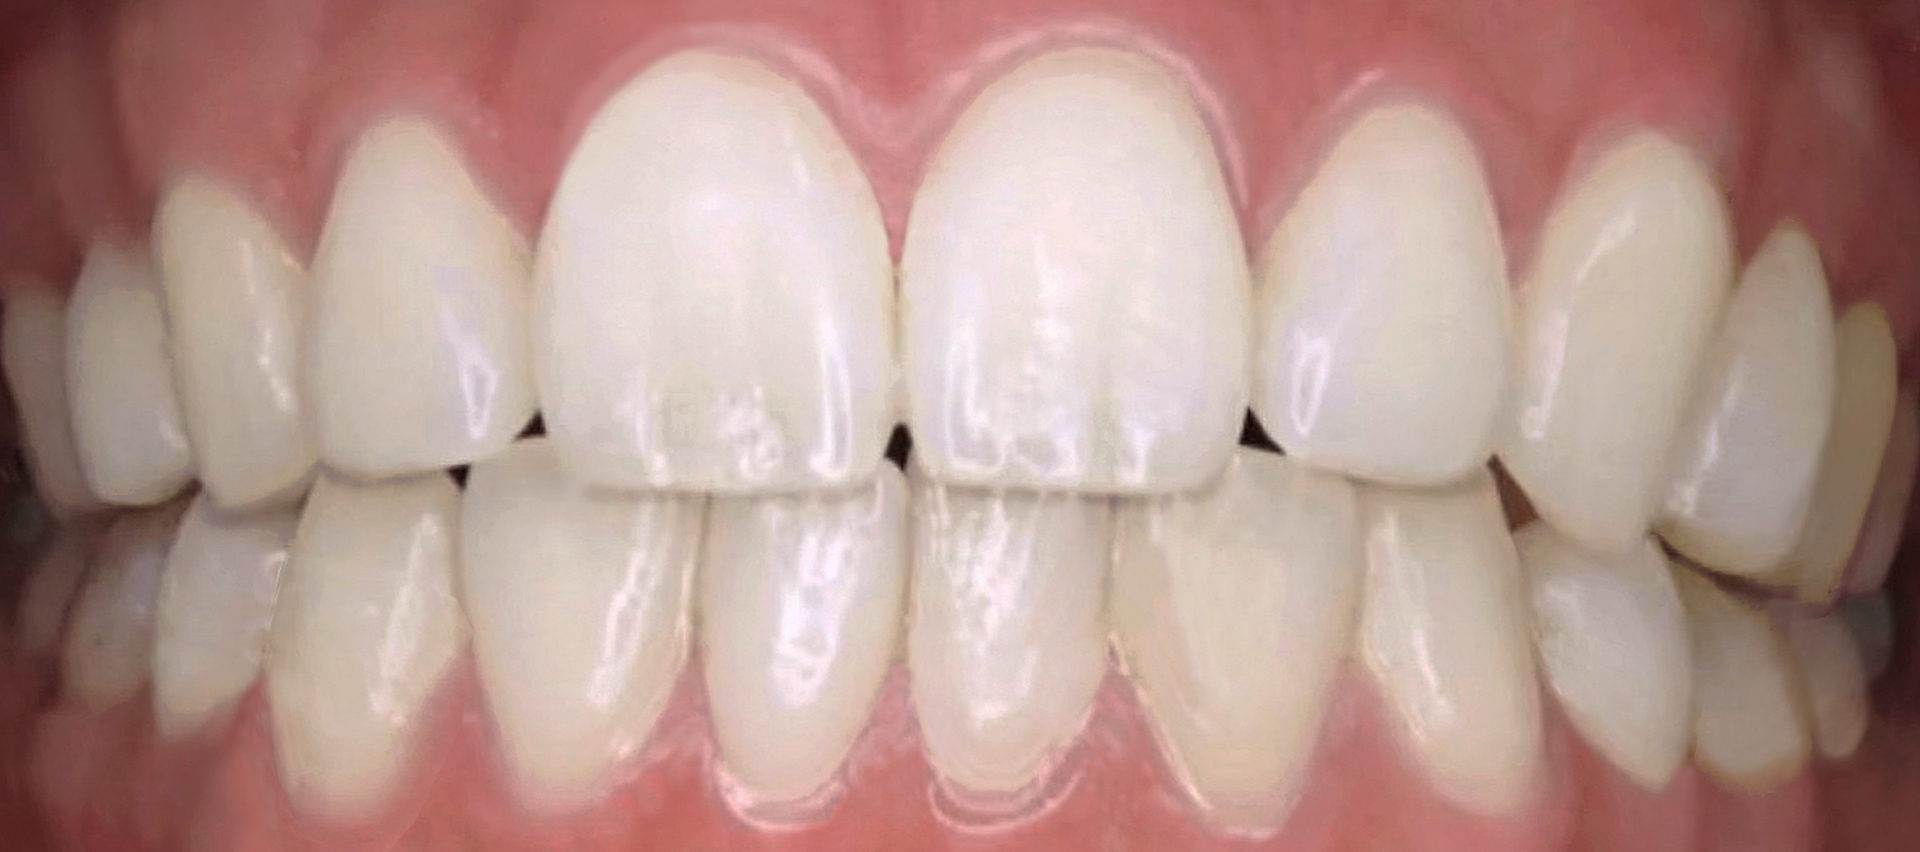

まず、虫歯や歯周病が今どんな状態なのかを確認します。歯にプラーク(歯垢)がたくさんついていないか、歯ぐきが腫れていないかなどをチェックします。